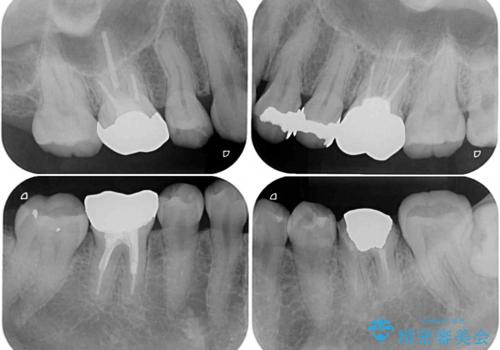

- 奥歯の銀歯が外れたことをきっかけに、全ての銀歯をセラミックに替えたいとのことで来院された患者様です。

第一大臼歯4本と、メタルインレーが装着されている2歯をセラミッククラウンならびにセラミックインレーにて補綴治療・修復治療を行うこととしました。

口腔内から、土台も含め銀歯がなくなったことでメタルフリーとなりました。